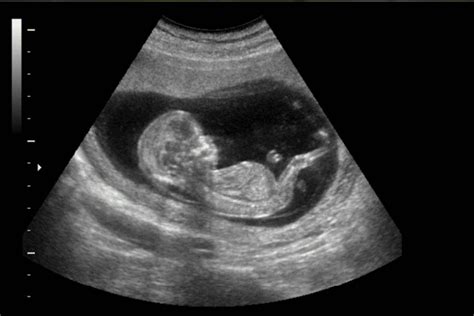

Las pruebas de diagnóstico prenatal son fundamentales. Existen diversas técnicas de cribado (screening) y diagnóstico. Las técnicas de cribado evalúan el "índice de riesgo" para determinadas anomalías, mientras que las técnicas de diagnóstico confirman la presencia del defecto. Estas pruebas se realizan sistemáticamente para detectar posibles riesgos y se combinan con análisis de sangre y técnicas de imagen como la ecografía y, en ocasiones, la resonancia magnética fetal.

Si un cribado combinado o una prueba de ADN fetal en sangre materna detecta un riesgo, es necesario realizar pruebas invasivas (biopsia de corion o amniocentesis) para confirmar el estado cromosómico fetal. En caso de riesgo de enfermedades genéticas hereditarias, es conveniente una visita de asesoramiento genético y un estudio del ADN de los progenitores.